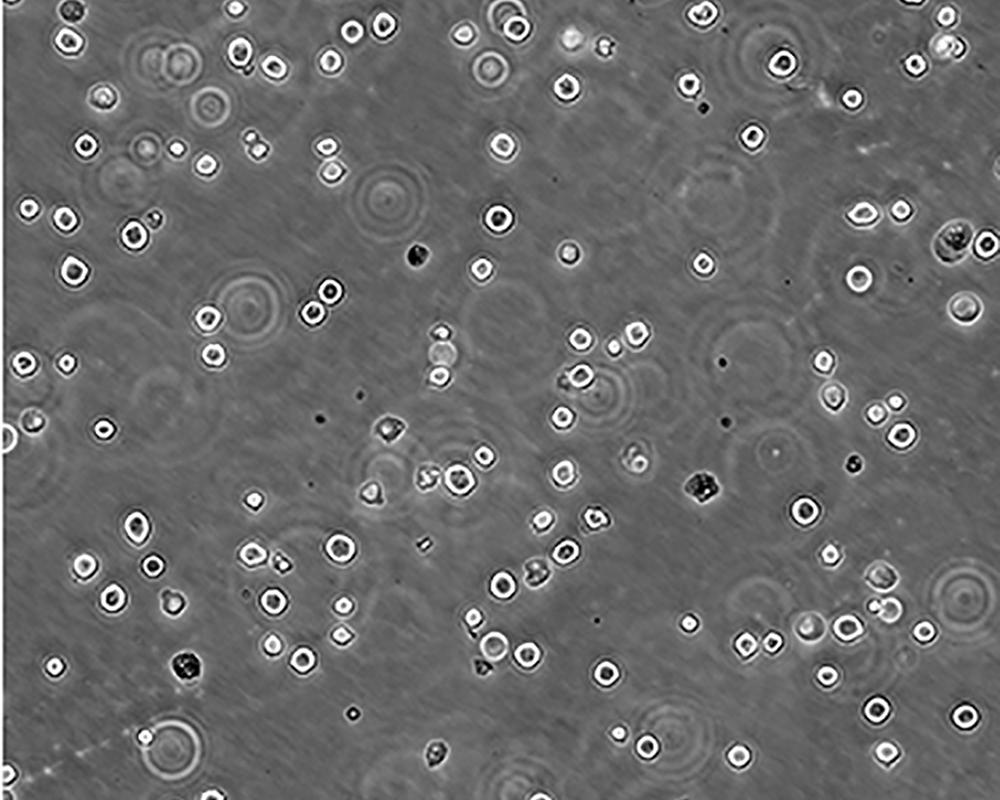

K-562 [K562]細胞

產品名稱 K-562 [K562]細胞

中文名稱 人慢性髓原白血病細胞

組織來源 慢性髓細胞白血病;女性

生長特性 suspension

形態特征 lymphoblast